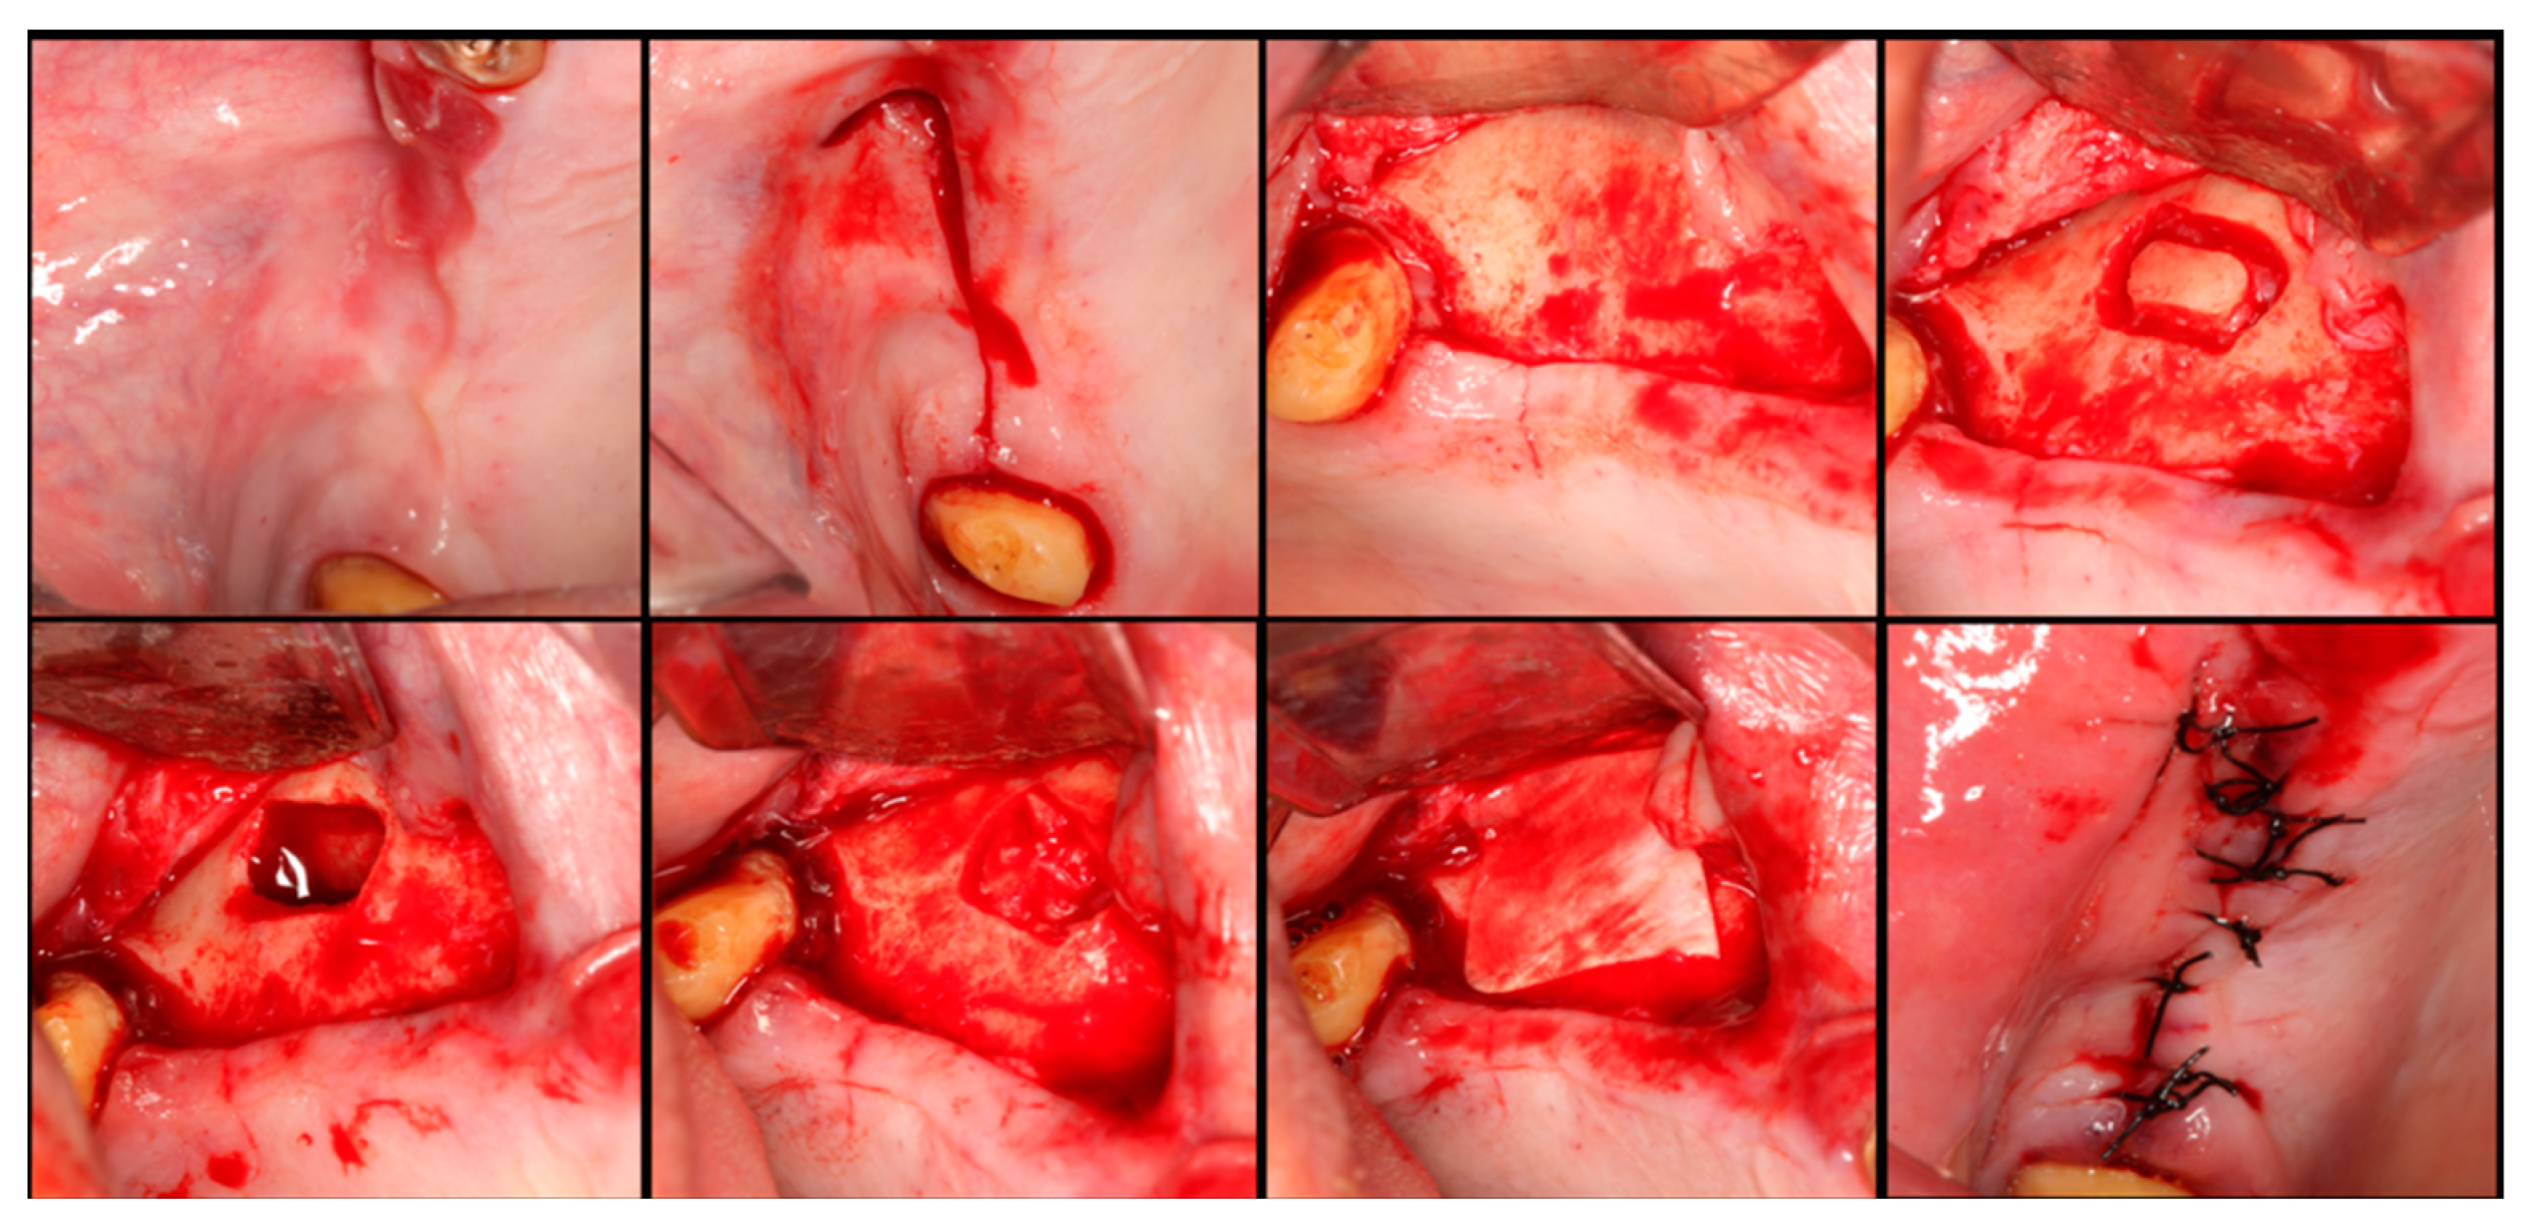

The surgical process, performed by the same surgeon, involved local anesthesia followed by incisions, flap detachment, osteotomy, and membrane elevation. Autologous bone from the mandibular branch (Figure 1) or the mental symphysis (Figure 2), or a porcine xenograft (Figure 3) were used as the graft materials for sinus augmentation. The protocol for this study involved using either two or three syringes of Oteobiol MP3, delivering a volume of approximately 2 to 3 cc per sinus. The contralateral sinus received a similar amount of autologous bone, either from the mental region (desmal with probably some bone of enchondral origin) or the mandibular ramus (desmal origin). Figure 3 and Figure 4 depict one example from each side of maxillary sinus augmentation treatment. Post surgery, the patients followed a prescribed protocol. After six months, a follow-up CT scan was conducted, and dental implants were placed. The final phase involved inserting healing abutments or prostheses, ensuring that no tooth–implant connections were established [20].

Figure 4. Step-by-step surgical demonstration of maxillary sinus elevation with autologous bone graft. In the first row, left to right: incision in the fourth quadrant, flap detachment, and lateral osteotomy. In the second row, left to right: accessing the sinus, filling with autograft, collagen membrane positioning, and sutures.